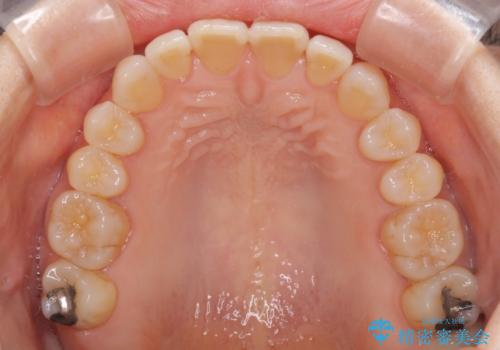

前歯の叢生と切端咬合 インビザラインによる矯正治療

上下前歯の先端同士が接触する切端咬合であったため、上顎は歯列を拡大し、下顎はIPR(歯と歯の間を削る)により叢生を解消しながら歯列を小さくすることとしました。

治療前から歯肉退縮が認められ、矯正治療により悪化する可能性が考えられたため、無理のない歯の移動と頻繁な経過観察を行いました。

切端咬合はスムーズに解消され、前歯の負担を軽減させることができました。